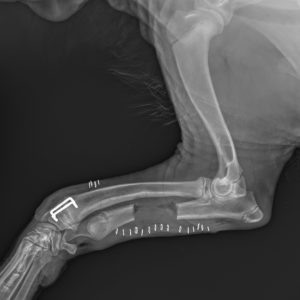

Poniżej prezentujemy zastosowanie klamer kostnych w leczeniu zespołu krzywej kości promieniowej u psa. Zdjęcia przedstawiają osteotomię kości łokciowej i częściową […]